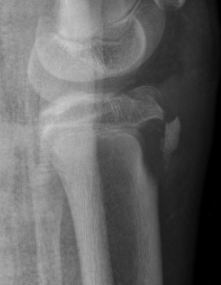

CT / MRI scan

CT scan - ensure fracture doesn't involve the physis / disrupt articular surface

Type IB